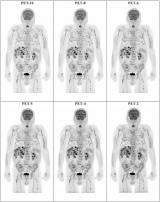

Immuno-PET预测患者对利妥昔单抗治疗的反应

根据荷兰的一个小组研究,锆-89(Zr-89)利妥昔单抗PET成像显示,有希望识别自身免疫性肺病患者是否会对免疫治疗产生反应。 2023-03-05 PET/CT辐射成像